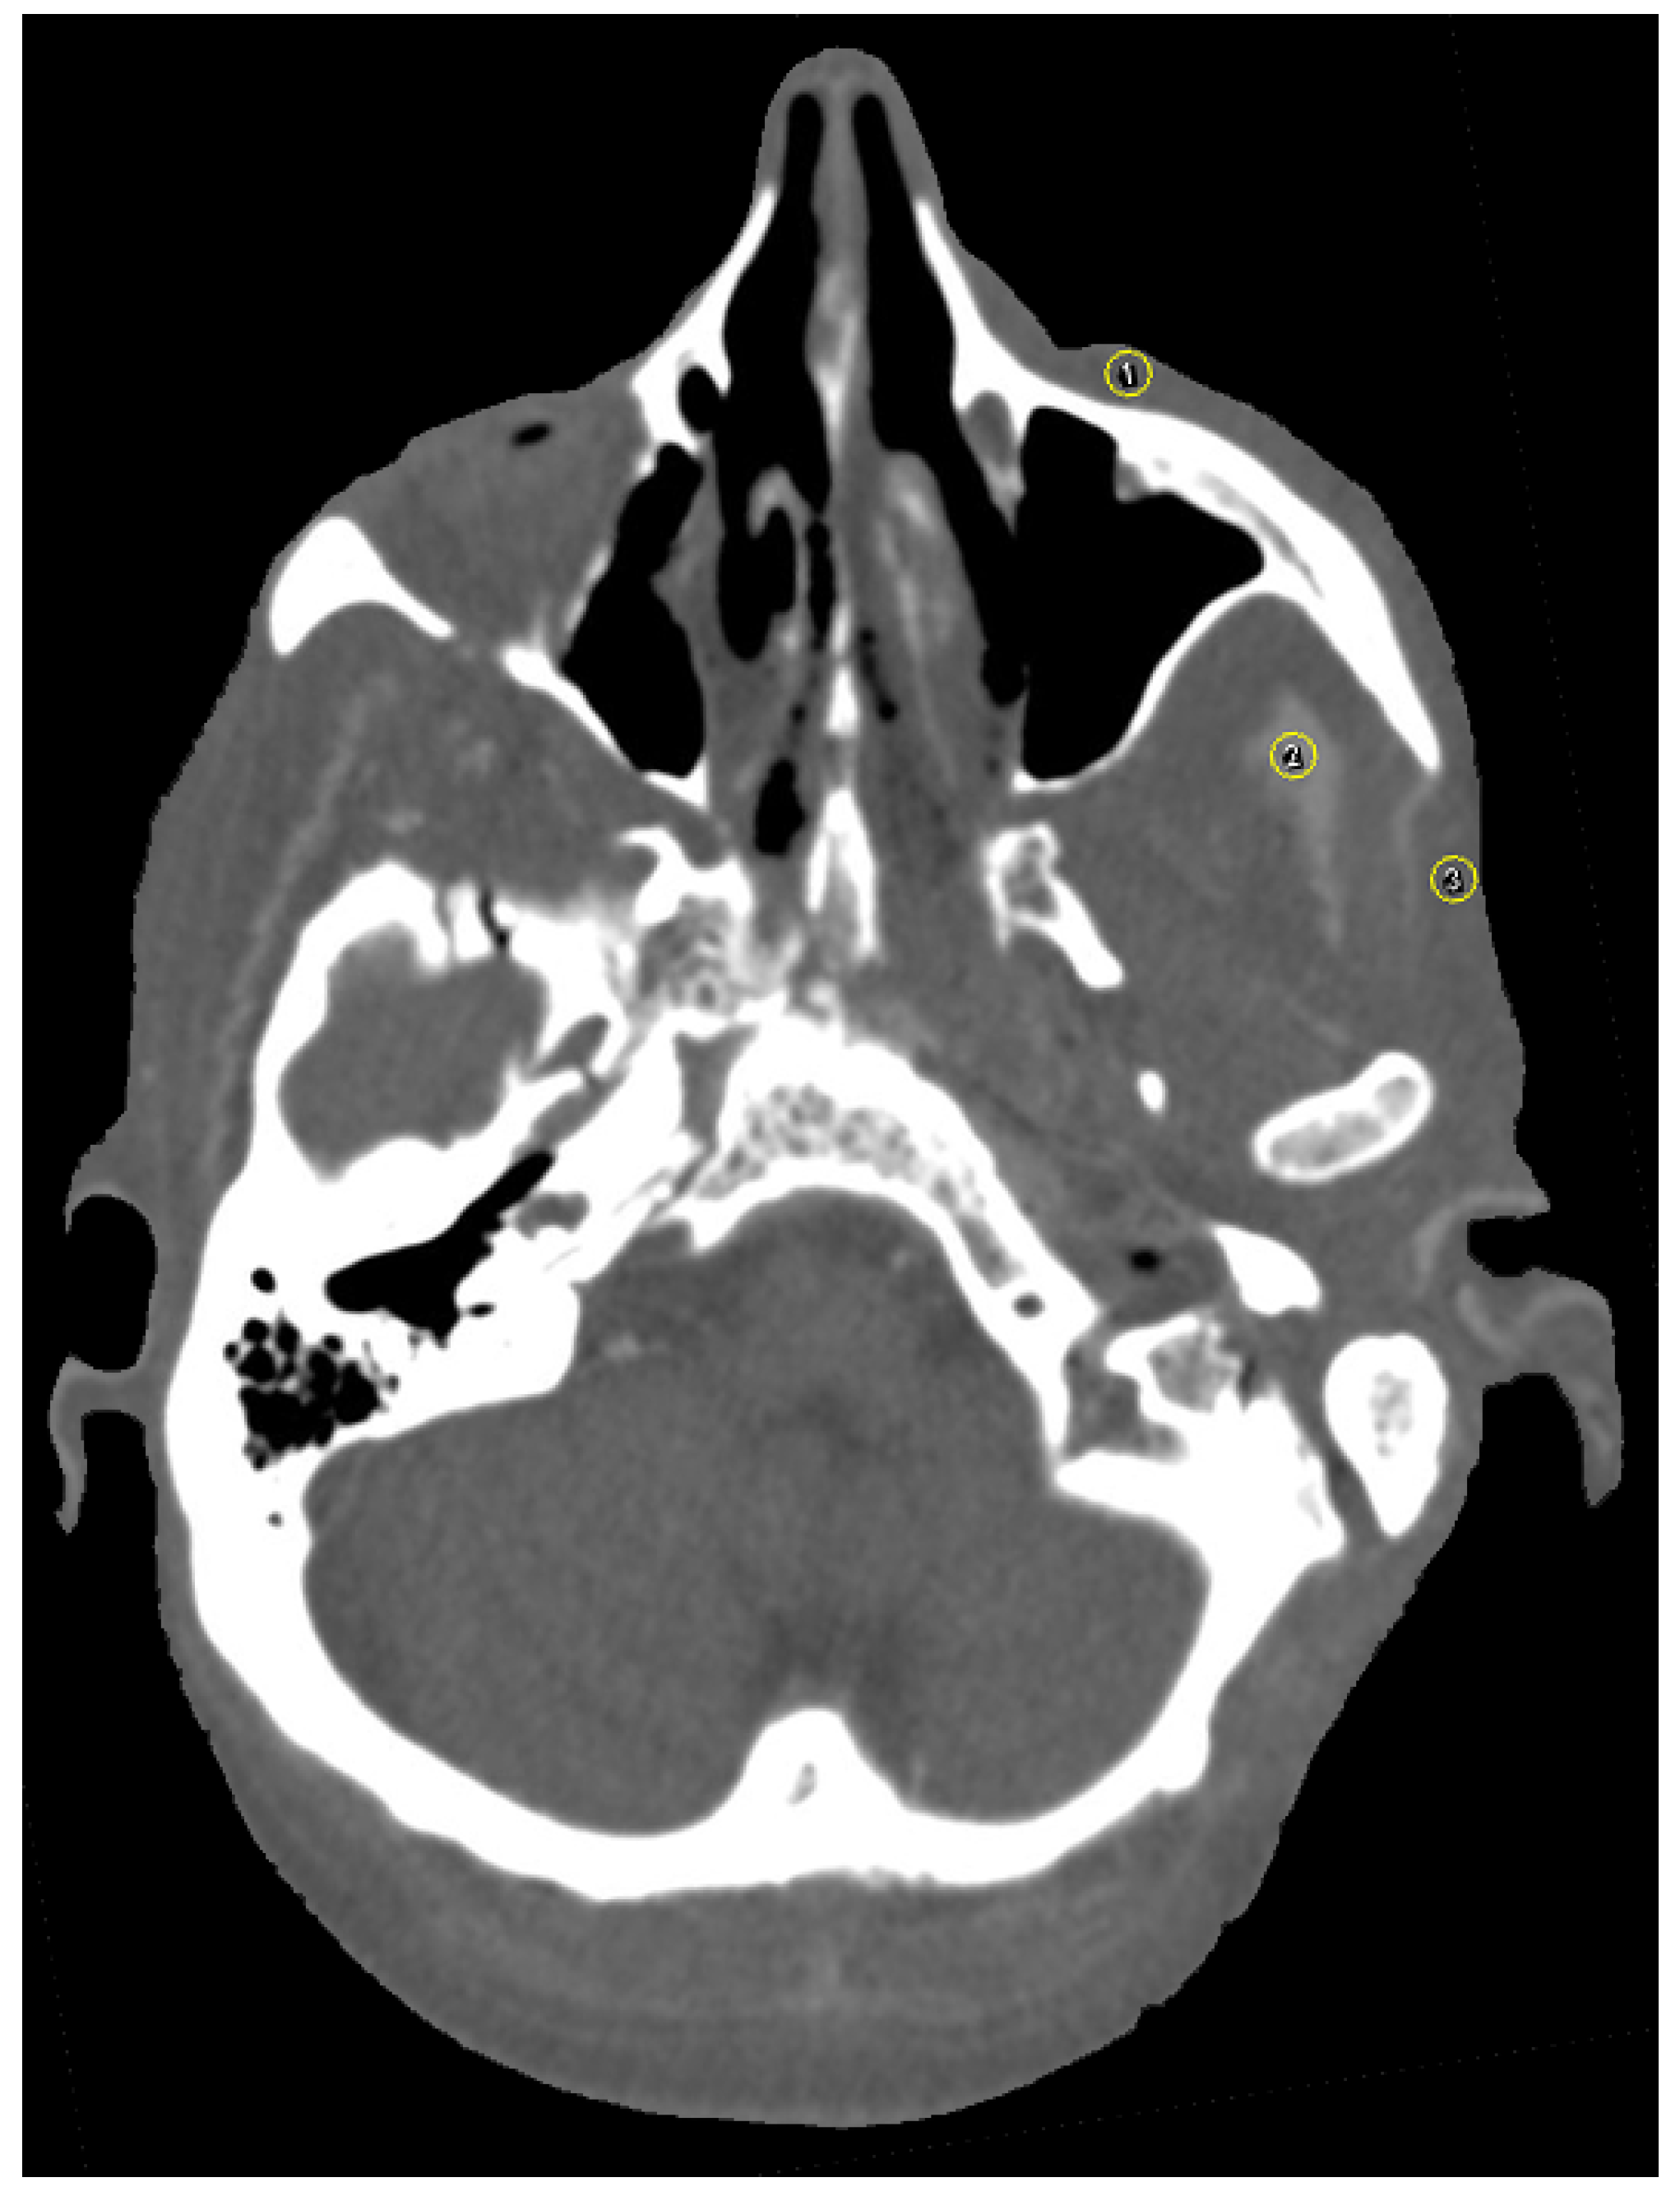

2.7. Image Analysis

3.1. Streak Artifacts

3.1.1. Implant Material

3.2. Blooming Artifacts